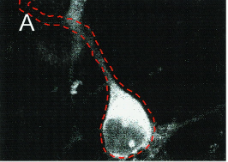

SubCellular Distribution of Rat Kir1.1 (ROMK1) in Neuron

The channel is clearly targeted to the membrane, and somatic staining is very bright. Dendritic staining is also present. This pattern agrees with that seen with antibody staining (not shown). Because each channel is associated with one GFP molecule, relationship of functional channel to fluorescence is quantitative [1855]